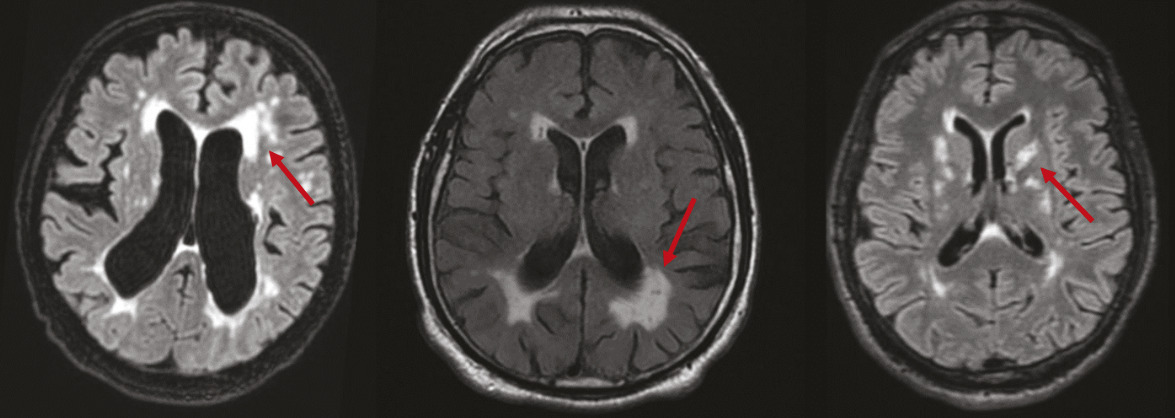

Lacunes, stigmates de lésions anciennes

Les lacunes sont des « trous » ovoïdes sous-corticaux, de 3 à 15 mm de diamètre, correspondant à une ancienne petite lésion ischémique ou hémorragique profonde dans le territoire d’une artère perforante, remplie de liquide céphalo­rachidien. La traduction à l’IRM cérébrale est une lésion en hyposignal T1 et T2, pouvant être entourée d’une couronne hyper­intense en T2 FLAIR (fig. 2). Si la taille le permet, il est possible de voir une hypodensité au scanner.5

Microbleeds, en hausse avec l’âge

Les microbleeds sont des effractions de sang dans le parenchyme cérébral. À l’IRM, ce sont de petites lésions rondes de 2 à 5 mm, homogènes et très hypo-­intenses en séquence de susceptibilité magnétique comme la séquence T2 écho de gradient (T2*) [fig. 3]. Ils ne sont pas visibles au scanner. Dans la maladie des petites artères cérébrales, ils sont typiquement localisés dans les territoires profonds du cerveau (ganglions de la base, tronc cérébral et cervelet).5